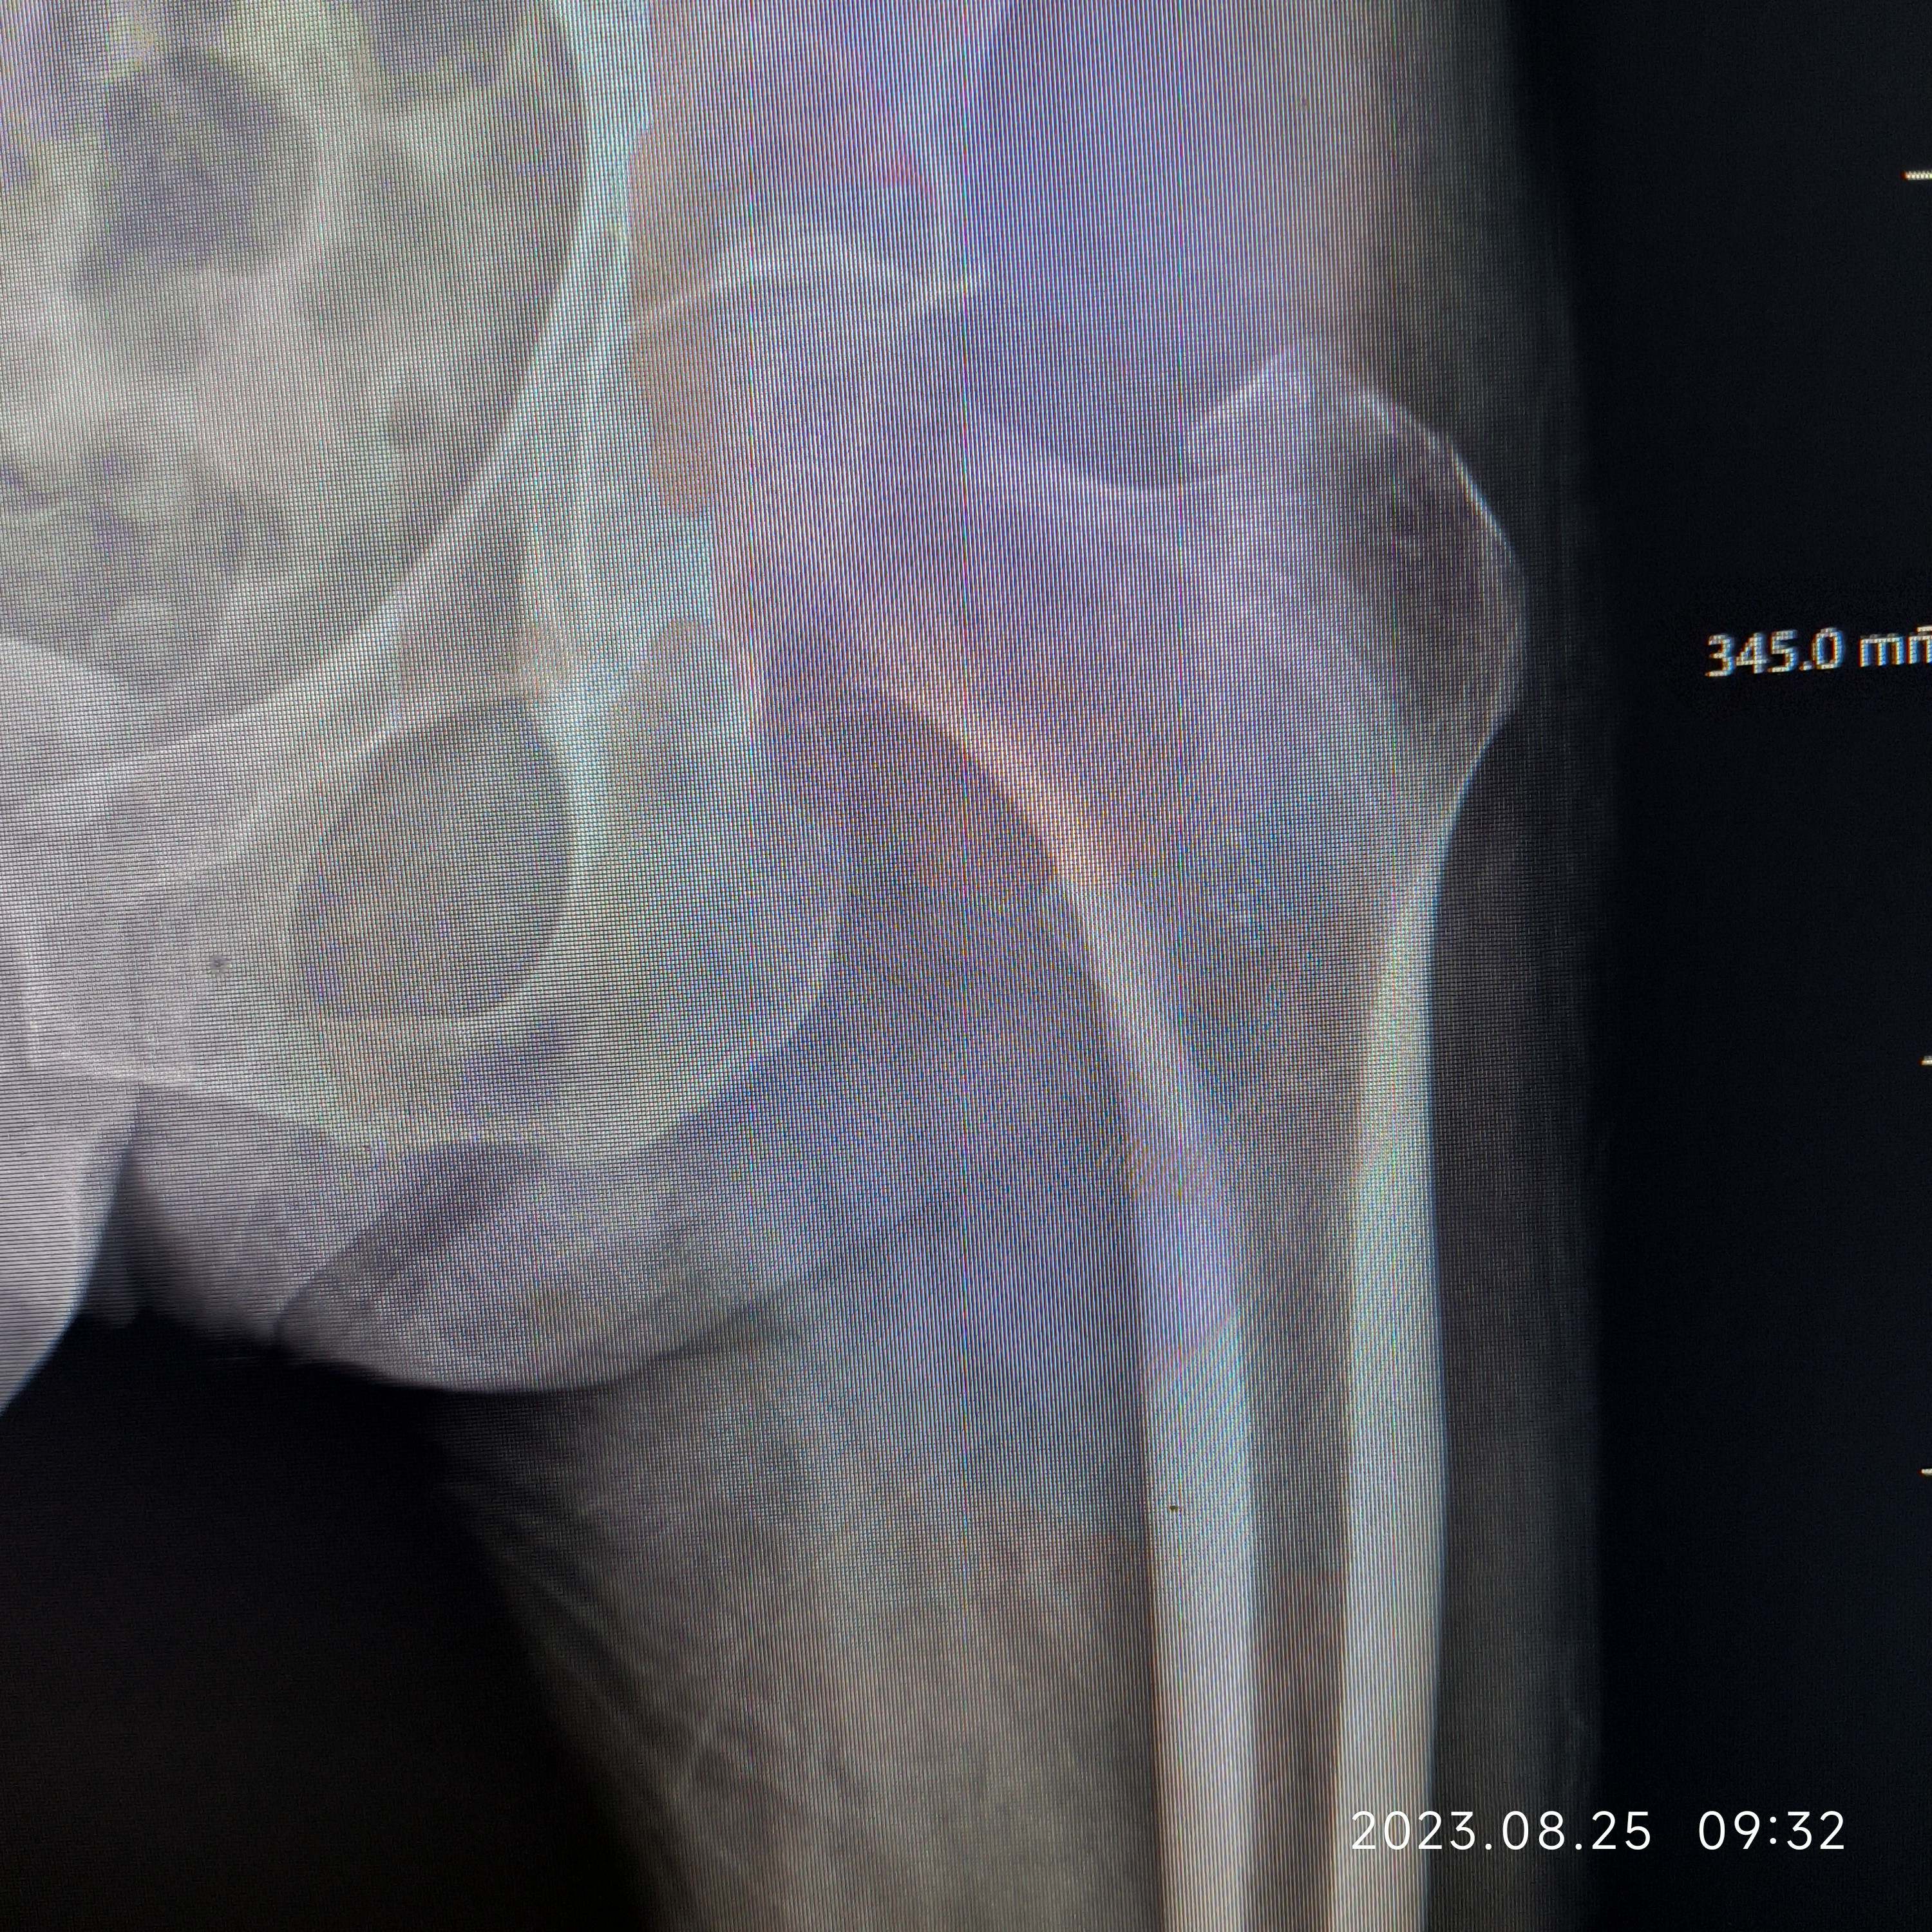

女,80岁,左股骨转子间骨折PFNa。病人营养状况一直不好,胃肠道接受能力非常差,稍微进食油腻基本上一天在10次左右腹泻(常备蒙脱石散、诺氟沙星…),家里老伴身体不好,子女忙都没法在家照顾,强烈要求手术,术前病人血色素6.5g,凝血正常,术中出血700ml左右,低血压报警一次,用了多巴胺后高压维持80mmHg左右,术后输了2U红悬+400ml血浆,第一天复查血色素5.9g,第二天复查血色素6.0g,术后1周复查血色素6.2g……病人精神状态一直还可以……